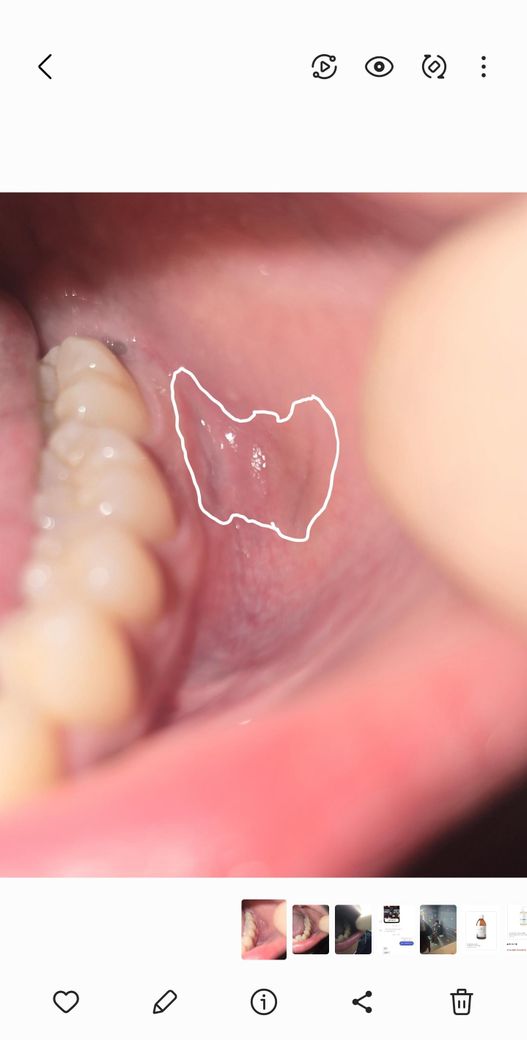

어금니 옆 볼 점막이 파여있는데 사랑니 때문인가요?

어금니 옆 볼 점막에 살짝 파여있고 통증없고 10일 정도 됐습니다. 병원가니까 사랑니 때문에 밀려서 그런거 같다고는 하시는데 궁금해서요 ㅠㅠ

• 1번 째 사진